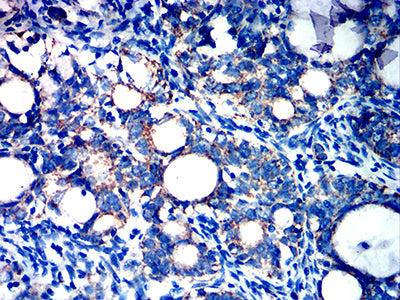

分类: 科研抗体货号: 32204别名: CD271; p75NTR; TNFRSF16; p75(NTR); Gp80-LNGFR应用: IHC,FCM反应种属: Human